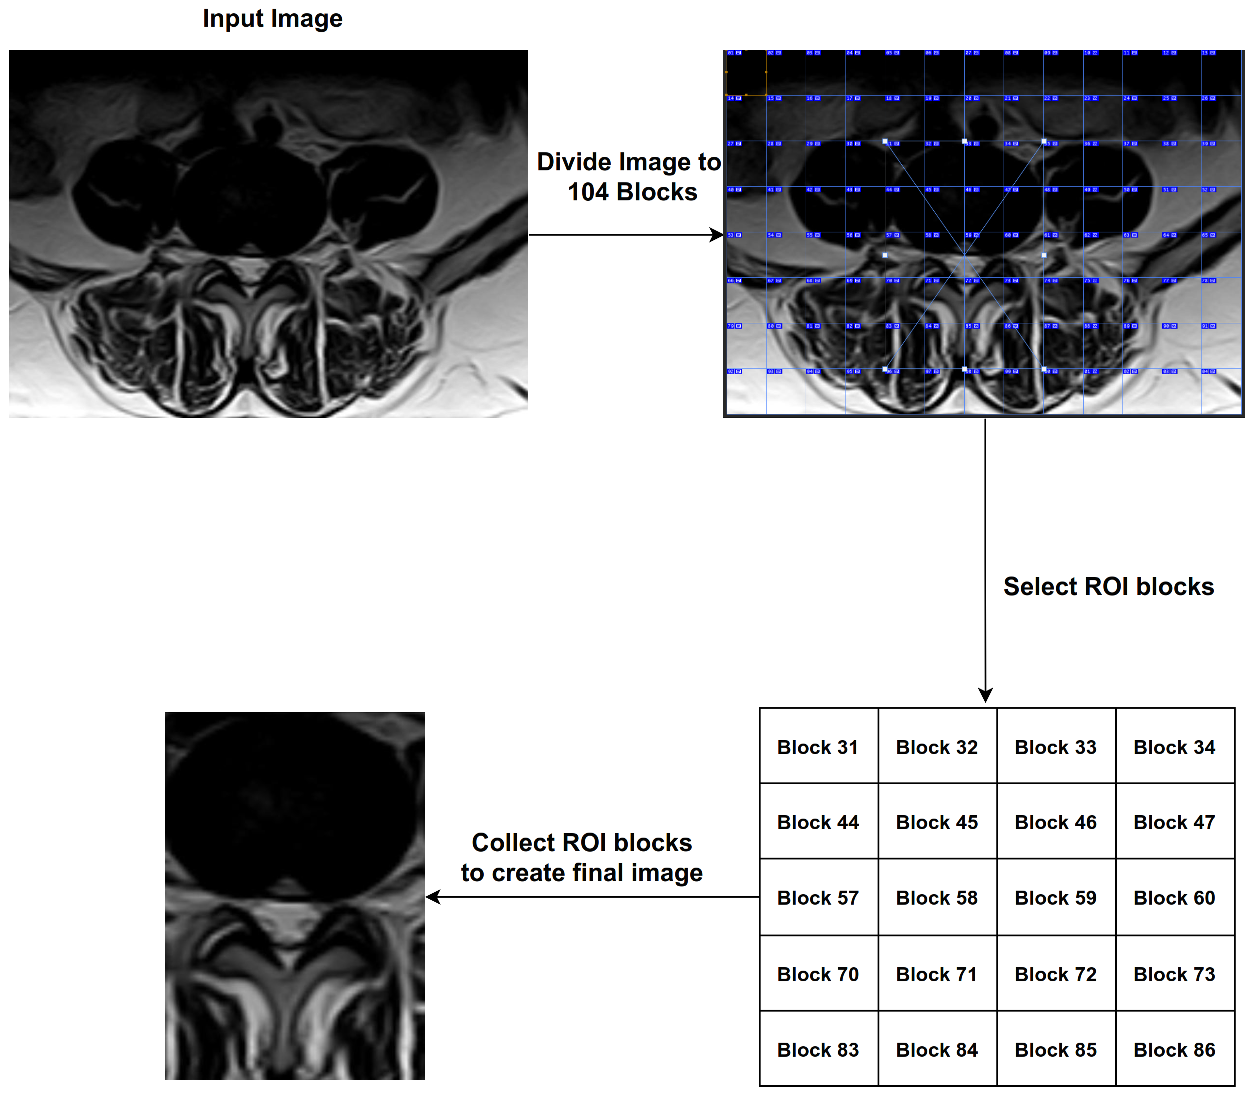

3.3. The Proposed ROI

The process of analyzing medical images is very complex and often the parts in the image overlap with the object to be diagnosed. For example, in the process of diagnosing images of lumbar spine discs, there are many shapes in the image such as the image of the intervertebral disc; the same is true in the diagnosis of spinal cord stenosis. Therefore, we proposed the ROI technique, which splits the image into many blocks, and we were able to identify the most important blocks. We divided the image with size (1061 width * 752 height) into 104 blocks and then selected 20 blocks with ROI, each of which has a size (82 * 94). Finally, we chose 20 blocks based on Equation (3).

Z = { 30 + ( 13 x ) + y : x { 0 , 1 , 2 , 3 , 4 } , y { 1 , 2 , 3 , 4 } }

where Z represents the block number to be selected. After completing this process, we obtained images that contain only the area of interest (see Figure 6). In Figure 7, we illustrate the steps to create ROI images.

Figure 6. Twenty blocks from an image, each one with size (82 * 94) used to create ROI.

Electronics 11 00085 g006

Figure 7. Steps to create ROI images.

Electronics 11 00085 g007